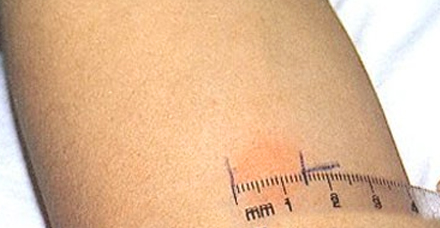

La chose la plus importante lors d'un test de Mantoux est de mesurer correctement le résultat. Le site d'injection devient souvent rouge et enflammé, un gonflement et un durcissement apparaissent. Le résultat de l'échantillon dans ce cas ne sera que le diamètre du joint, la taille de la rougeur n'affecte en rien le résultat et est une réaction individuelle.

Le diamètre de la papule est mesuré uniquement à l'aide d'une règle transparente rigide, puis ces tailles sont comparées aux normes:

- 0-1 mm - «réaction négative»;

- 2-4 mm - «réaction douteuse» (l'enfant fait partie du groupe à risque);

- à partir de 5 mm - «réaction positive» (forte probabilité de maladie, mais ils ne sont pas diagnostiqués avec un seul test de Mantoux, des études supplémentaires sont nécessaires);

- à partir de 17 mm - «réaction hyperergique» (signe grave de la maladie).